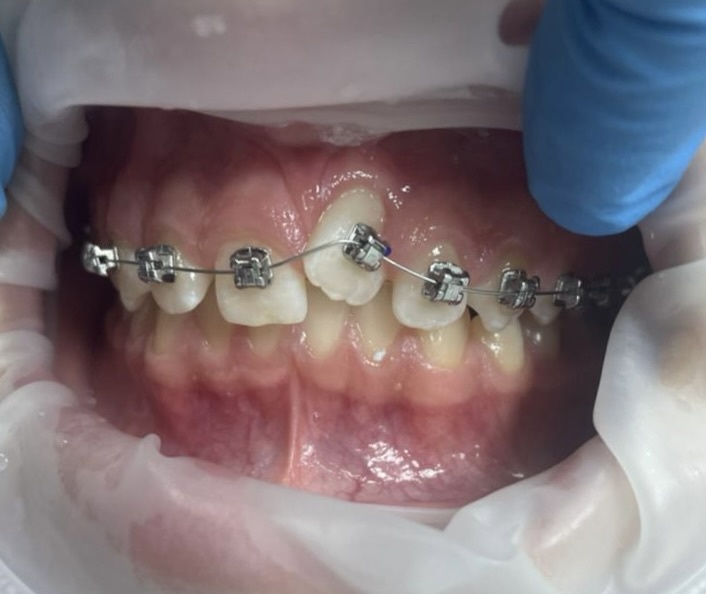

Ортодонт установила на верхнюю челюсть металлическую самолигирующуюся систему Damon Q и отправила пациентку на некоторое время (1.5 месяца) домой. Сделала фото на контрольном приёме:

Экструзия зуба 2.1 через 1.5 месяца после установки б\с